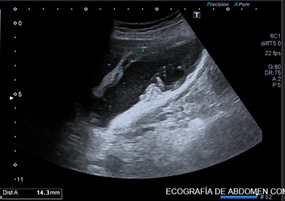

Exploramos con sonda convex en corte longitudinal en epigastrio una imagen ovalada de predominio anecoico de bordes bien delimitados que en corte transverso se extiende longitudinalmente por la linea media de forma ovalada y de diametro mayor a 93,3 mm que presenta contenido hipoecoico en semiluna adherido a pared altamente sugerente de aneurisma aortico con trombo endomural que en algunas zonas ocupa más del 50% de la luz del vaso.